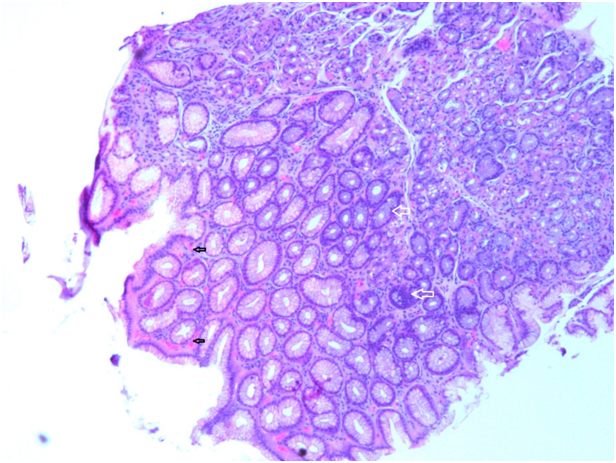

A 79year old chronic smoker (60 pack years and ex-smoker for 30years) male with no significant medical history was admitted for painless, persistent, progressive odynophagia for two weeks. He reported loss of appetite, change in voice, and unintentional loss of 40 pounds with loss of taste in two months associated with constipation. He denies nausea, vomiting, abdominal pain, lower abdominal discomfort, chest pain, cough, palpitation, hematemesis, hemoptysis or melena. Physical examination was unremarkable except mild tenderness in left lower quadrant, no guarding or rigidity, bowel sounds heard in all four quadrants but no palpable organomegaly. Basic metabolic panel and Liver function test are within normal limit. CEA was 1162 and CA 19.9 was 5885.3. Abdomen X-ray showed moderate amount of stool in the colon and chest X-ray showed bilateral rounded opacities of uncertain etiology. Due to anemia work up and negative fecal occult blood, CT scan of abdomen with contrast was done and showed neoplasm of distal sigmoid colon and rectum with extension along inferior mesenteric artery, para-aortic, retroperitoneal, and pelvic lymphadenopathy, metastatic disease to the liver, lungs and bones, and thrombosis of the right portal vein. Later, EGD showed LA class D esophagitis seen at 25cm from incisor extending up to 40cm. Overlying blackish exudate was seen at area of the esophagitis (Figure 1). Colonoscopy showed large, erythematous, near obstructing friable mass at the recto-sigmoid junction. Multiple biopsies were taken from the mass. In order to relieve lumen obstruction, metallic colonic stent was placed .Pathological report from Esophagus showed squamous esophageal mucosa with mild acute nonspecific esophagitis (Figure 2) (Figure 3) but no fungus detected by PAS stain. Antrum and body biopsy report showed mild chronic nonspecific gastritis. Recto-sigmoidal biopsy showed Infiltrating adenocarcinoma (Figure 4). Surgery team was consulted but the patient is not a candidate for surgical procedure. Oncology was consulted for aggressive treatment but the patient and family appreciated palliative care and he is on enoxaparin for portal vein thrombosis.

Figure 1 Endoscopic view of the middle esophagus revealing black mucosa with friable tissue.

Figure 2 Esophageal biopsy (H&E, 20x) showed demarcation line in the upper submucosa with a predominance of neutrophilic granulocytes and scattered macrophages along with platelet thrombus in the small submucosal vessel.

Figure 3 Esophageal biopsy (H&E, 40x) showed demarcation line in the upper submucosa with a predominance of neutrophilic granulocytes and scattered macrophages along with platelet thrombus in the small submucosal vessel.